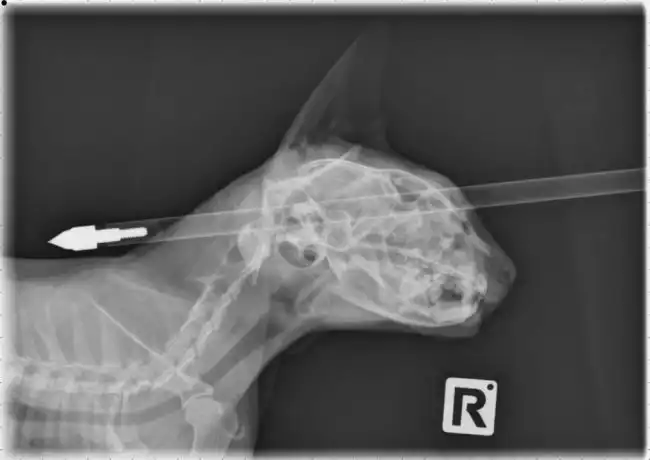

Ветеринары спасли кошку

Животинке очень повезло, что ранение не задело жизненно-важные органы.